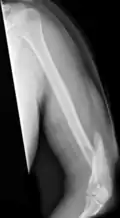

A transverse fracture of the humerus shaft -